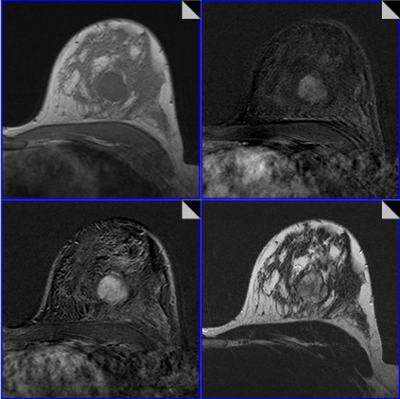

All MR scans were acquired on a 1.5-tesla scanner and included dynamic T1-weighted contrast-enhanced images and T2-weighted images with turbo-spin echo (TSE) sequences without fat saturation. A total of 1,012 patients and 1,084 histologically verified lesions (648 malignant, 436 benign) were included in the study.

Images were read in consensus by two of a total of six radiologists with experience reading more than 500 breast MRI studies. Readers were blinded to histopathological results, and the radiologists used a predefined lexicon of 17 categorical descriptors to describe what they saw on the images.

Of the 17 descriptors, four were related to contrast agent kinetics (initial phase, delayed phase, internal enhancement, and blooming sign), while the remaining 13 dealt with morphology. Because 12 descriptors were determined not to add diagnostic accuracy, the researchers elected to use only five in the classification tree:

- Root sign (absent or present)

- Delayed phase (persistent, plateau, or washout)

- Margins (irregular or smooth)

- Internal enhancement (inhomogenous, centripetal or homogenous, centrifugal)

- Edema (absent, diffuse bilateral or perifocal, diffuse ipsilateral)

After reading the image and describing their findings, the radiologists then consult the tree to determine the probability of lesion malignancy using the five descriptors they included in the report.